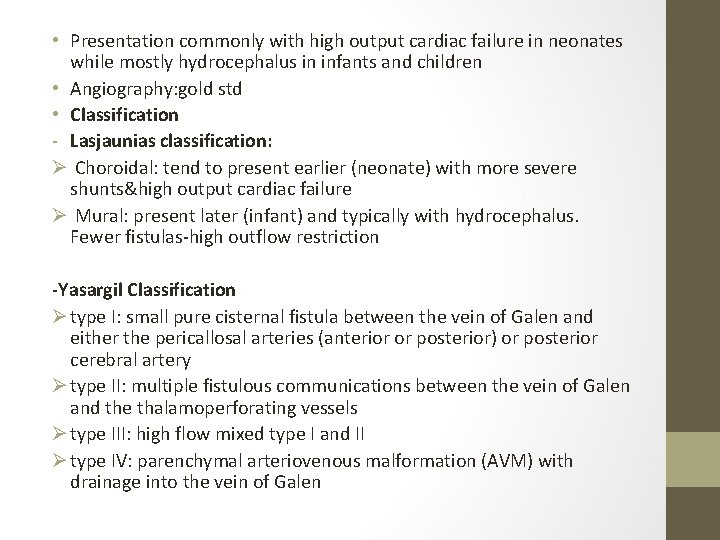

• Presentation commonly with high output cardiac failure in neonates while mostly hydrocephalus in infants and children • Angiography: gold std • Classification - Lasjaunias classification: Ø Choroidal: tend to present earlier (neonate) with more severe shunts&high output cardiac failure Ø Mural: present later (infant) and typically with hydrocephalus. Fewer fistulas-high outflow restriction -Yasargil Classification Ø type I: small pure cisternal fistula between the vein of Galen and either the pericallosal arteries (anterior or posterior) or posterior cerebral artery Ø type II: multiple fistulous communications between the vein of Galen and the thalamoperforating vessels Ø type III: high flow mixed type I and II Ø type IV: parenchymal arteriovenous malformation (AVM) with drainage into the vein of Galen